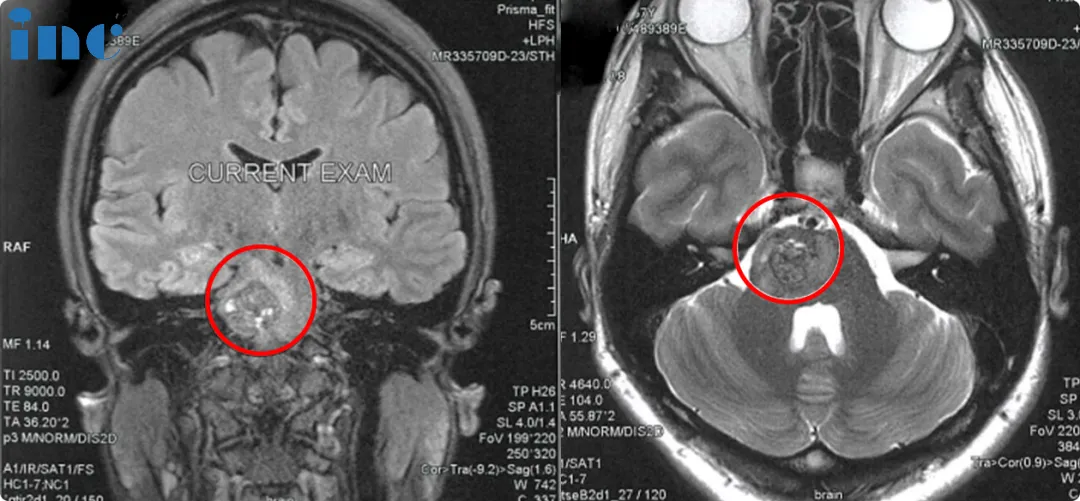

“海绵状血管瘤被切除了,所以健康的脑组织有膨胀,有点像海绵一样张开。这是正常的,海绵状血管瘤总是这样。但重要的是,它没有残瘤。”

“没有了,没有残留!”巴教授耐心解答着佩珊,用越发流利的中文回答她。